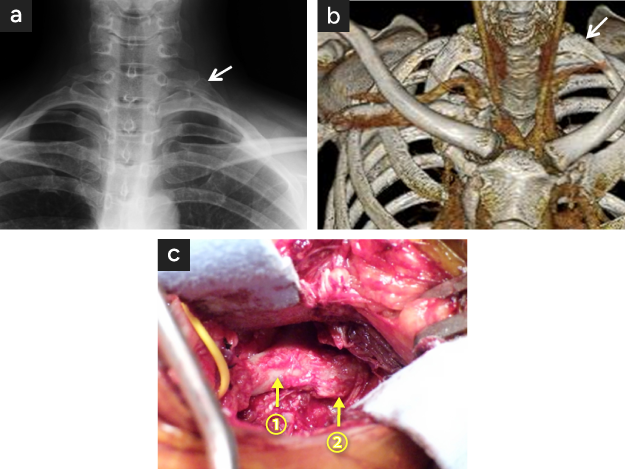

図18

図18. 頚肋を伴う左動脈性胸郭出口症候群

• 左頚肋typeIII XP(矢印)

• 左頚肋typeIII CT(矢印)

• 鎖骨上切開創からみた第一肋骨(矢印)とそれに付着するtypeIIIの頚肋(太矢印)